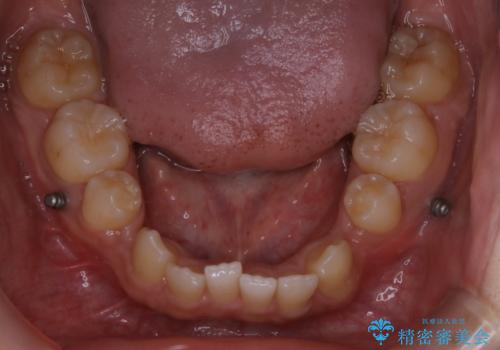

インビザライン単独でここまでできる!!抜歯矯正

- 治療計画

- マウスピースによる矯正治療をご希望された方です。歯のガタつきが大きかったため、ワイヤーによる抜歯矯正をご提案しました。どうしてもマウスピースが良いとの強いご希望があったため、治療の途中でワイヤー治療に切り替える可能性もあることを十分ご理解いただいた上でインビザラインによる抜歯矯正治療を行いました。

1日20時間以上、正しくインビザラインを使用して頂いたおかげで、ワイヤーに切り替えることなく矯正治療を終了することが出来ました。周囲からも歯並びがすごく綺麗になったと言われたのことで大変ご満足いただけました。